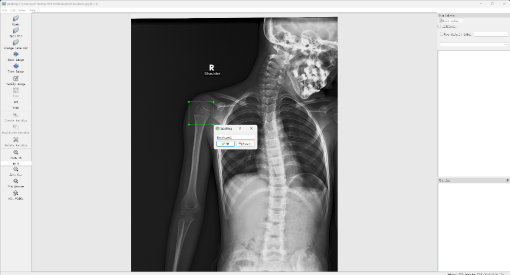

骨折等骨损伤的X光片数据集从互联网中收集X光图像,对收集到的图像进行筛选,去除质量低下、不清晰或者与目标类别无关的图像。收集到的原始图像数据需要经过标注才能用于训练,数据标注是将图像中的每个目标用边界框标出,并为其分配相应的类别标签,这一步骤对于模型学习识别和定位目标至关重要,本设计选择LabelImg工具进行标注,如图3.1所示。

4 应用设计

如图4.7和图4.8分别为同一张骨折X光片输入YOLOv5模型和YOLOv8模型推理后的结果,可以清晰地看到在YOLOv5模型中只检测出X光片中的一处骨折,而YOLOv8模型中则检测出两处骨折等骨损伤处,而这两处检测目标较小较模糊,进一步体现出了YOLOv8训练的模型的优秀性能,其不仅能够在模糊背景的图片中检测出微小的骨折等骨损伤目标,而且因为其较高的召回率,使得其能够尽可能地检测出所有的目标,也就是图中的两处骨损伤,对于严谨的医学影像分析领域,其具有较高的符合性,因此最终选择YOLOv8训练的模型作为该骨科诊断系统的深度学习核心模型。